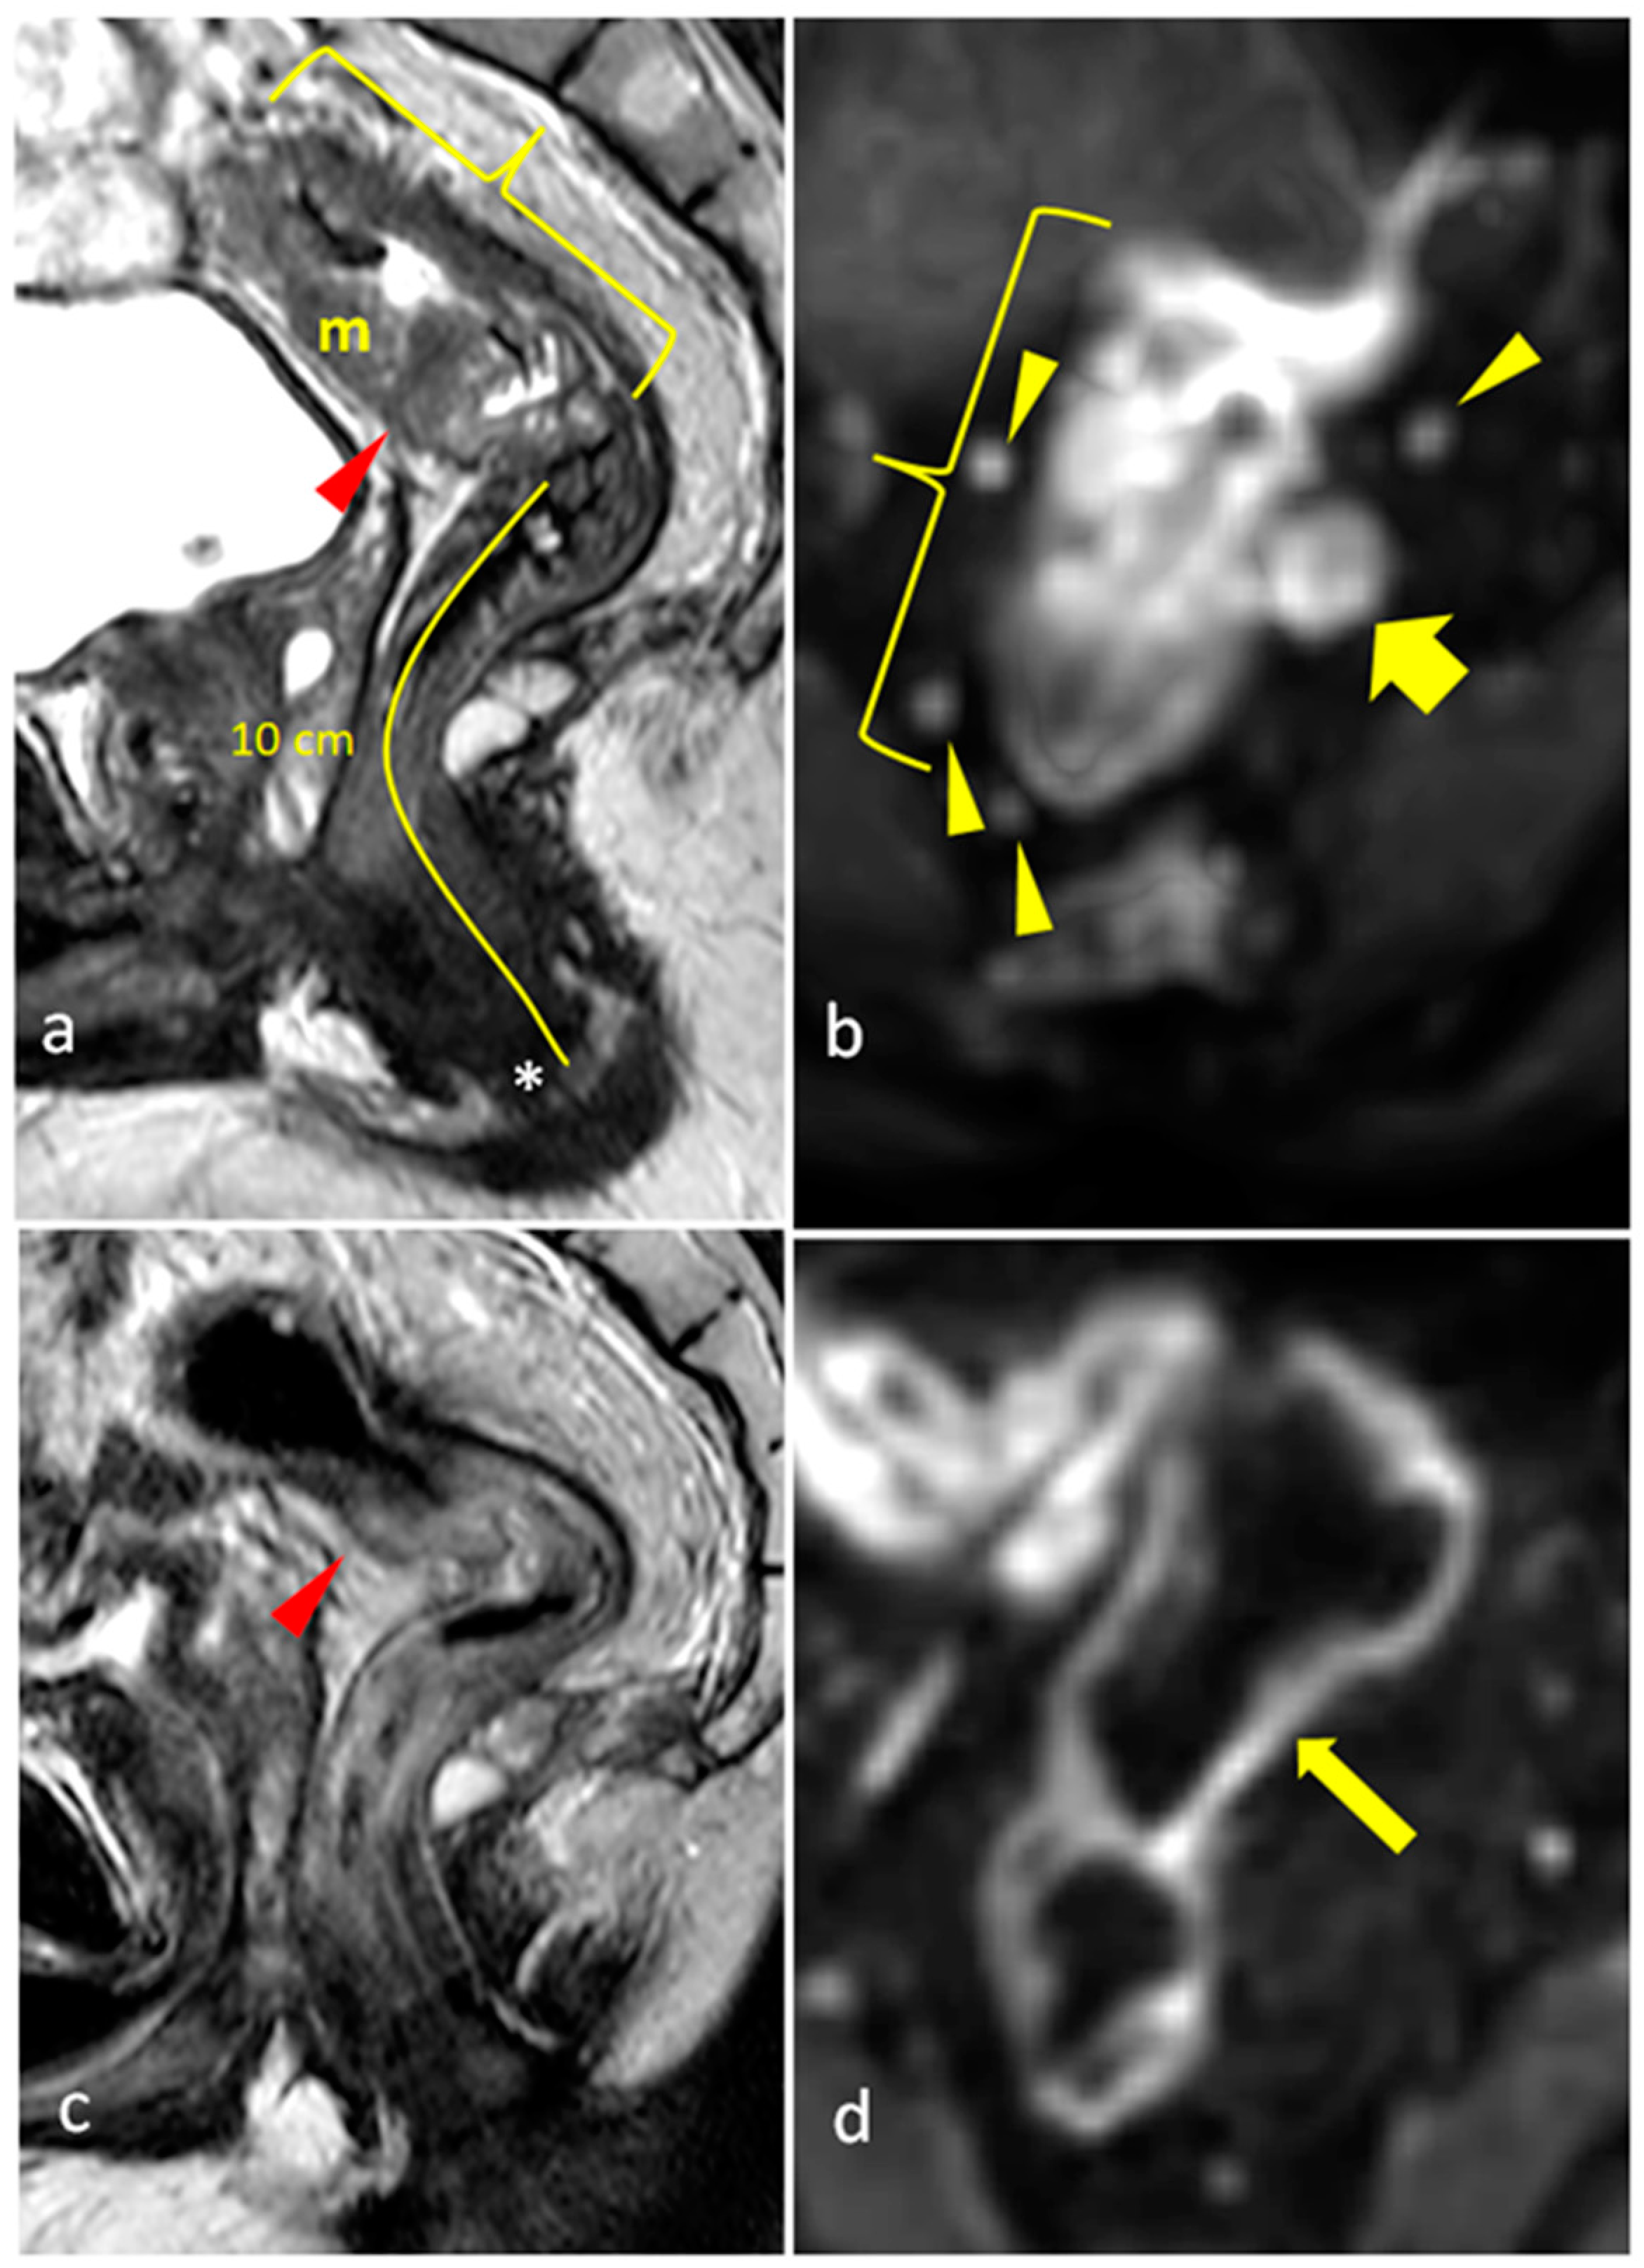

- Kalisz, K.R.; Enzerra, M.D.; Paspulati, R.M. MRI Evaluation of the Response of Rectal Cancer to Neoadjuvant Chemoradiation Therapy. Radiographics 2019, 39, 538–556. [Google Scholar]

- Jang, J.K.; Choi, S.H.; Park, S.H.; Kim, K.W.; Kim, H.J.; Lee, J.S.; Kim, A.Y. MR tumor regression grade for pathological complete response in rectal cancer post neoadjuvant chemoradiotherapy: A systematic review and meta-analysis for accuracy. Eur. Radiol. 2020, 30, 2312–2323. [Google Scholar] [CrossRef]

| mrTRG | 1 | Complete Radiologic Response (i.e., no evidence of tumor) |

| 2 | Good Response (i.e., dense >75% fibrosis with no obvious residual tumor) | |

| 3 | Moderate Response (i.e., >50% fibrosis or mucin with a minority of visible tumor) | |

| 4 | Slight Regression (i.e., <50% fibrosis or mucin with a majority of visible tumor) | |

| 5 | No post-treatment changes | |